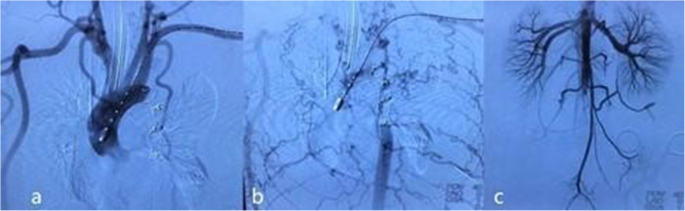

Then, a novel approach was proposed. In the first step, a right-side axillary-femoral bypass was performed. An 8 mm * 60 mm vascular graft (GORE INTERING Vascular Graft, GORE, USA) was sutured at the right infraclavicular region, with a right femoral end-to-side anastomosis. The graft was tunneled subcutaneously along the midaxillary line to prevent graft entanglement due to torso flexion. In the second step, transcatheter aortic occlusion was performed via left femoral access. Left femoral access was obtained percutaneously, and then, a 10F long sheath (Cook, Bloomington, Indiana, USA) was advanced from the left femoral artery over a 0.035 in. superstiff guidewire (Amplatz Super Stiff, Boston Scientific, USA) through the lesion segment. Two 18/16 mm PDA occluders (Starway Medical Technology Inc., Beijing, China) were placed proximal and distal to the lesion segment to block flow. The proximal occluder was placed exactly between the origin of the left subclavian artery and the narrowest segment, and the distal occluder was placed 30 mm beyond the site of the pseudoaneurysm, where the aortic wall was morphologically normal. Postoperative angiography demonstrated patent bypass and the satisfied position of the occluders. Ruptured pseudoaneurysm was successfully excluded. No residual leakage was found. The upper abdominal aorta still filled in an anterograde manner by extensive collateral vessels. The perfusion of the abdominal visceral arteries was sufficient. The right iliac artery was filled in a retrograde manner by the bypass vessel. The anterograde and retrograde blood flows intermixed at the distal abdominal aorta (Fig. 2). After the procedure, the vital signs became stable, and the blood pressure was 125/71 mmHg in the upper limbs and 116/73 mmHg in the lower limbs. A 6F Perclose ProGlide suture closure device (Abbott Vascular, Abbott Park, Ill) was deployed at the access point. In the third step, the hysterotomy procedure was performed by an obstetrician/gynaecologist.

Post-operative angiography. a. Antegrade angiography of the ascending aorta demonstrated successful exclusion of the coarcted aortic segment and pseudoaneurysm. b. Antegrade angiography of the ascending aorta in the late phase revealed that the upper abdominal aorta was filled in an antegrade manner from extensive collateral circulation. c. Abdominal aortic angiography demonstrated that anterograde and retrograde blood flow intermixed at the distal abdominal aorta